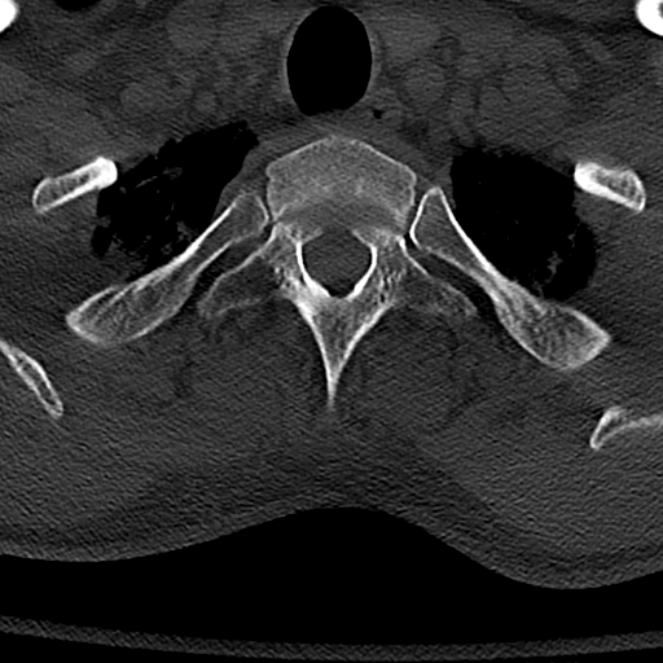

Another fracture was reported in 1900, by kissinger (2). The occipital condyles are undersurface protuberances of the occipital bone in vertebrates, which function in articulation with the superior facets of the atlas vertebra.

Clinical decision rule and surgical management. Occipital condyle fractures (ocfs) can easily be missed because the clinical manifestation is highly variable and the results of physical examination are usually nonspecific. Occipital condyle fractures were present in 2.5% of these patients.

Morphology and treatment of occipital condyle fractures. Clinical decision rule and surgical management. 2011 epub ahead of print. So far, the detection rate in trauma patients in a centre of the highest care level (level 1 trauma centre) has been 6. We performed fusion surgery from the occiput to c5 without decompression of c1. Surgical treatment may be required if the condyle fracture is accompanied by atlantooccipital dislocation. Fractures of the occipital condyles probably occur more frequently than is appreciated since they are not visible on plain radiographs. Treatment should depend on whether the fracture is stable or not. There is insufficient evidence to support diagnostic standards. The diagnosis and treatment of fractures of occipital condyle. • external immobilization for the treatment of isolated fractures of the axis body is recommended. Of the six treated by the authors, one death (by pontine hemorrhage) type i and ii are stable, and the authors recommend treatment with a semiconstrained cervical orthosis. One occipital condyle 14 cervical. Unfortunately, condyle fracture generally cannot be diagnosed with. Treatment with external cervical immobilization is recommended. Spine (phila pa 1976) 13: Occipital condyle fractures (ocfs) can easily be missed because the clinical manifestation is highly variable and the results of physical examination are usually nonspecific.